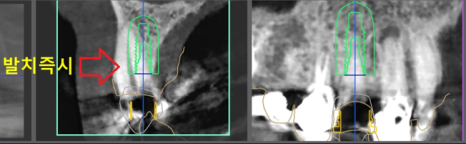

디지털 임플란트 진단을 하면서,

apical lesion(뿌리 염증) 이 있는것이 관찰이 되며

당일 발치 후 즉시식립을 하기로 했습니다.

그래서, 위에서 볼 수 있는 사진들 처럼

여러가지 방법을 동원하여 현 상황을

정확히 분석을 해야 되겠죠.